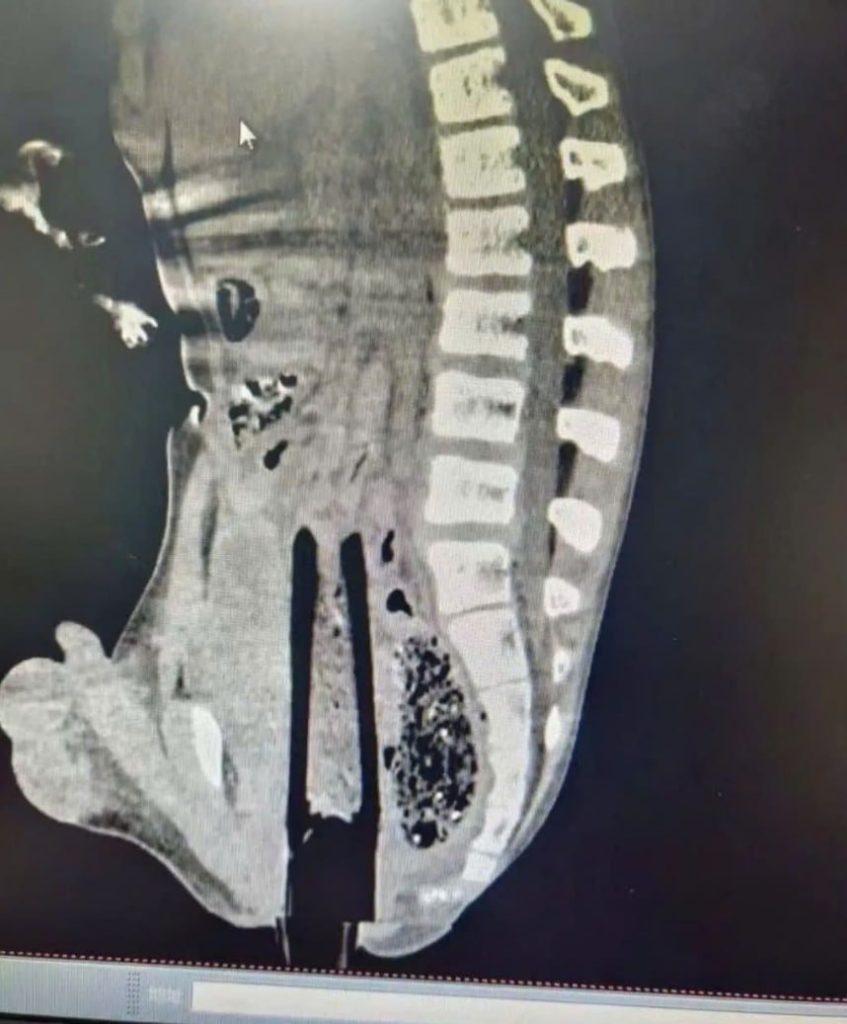

- Hình CT scan cho thấy dị vật hình trụ dài cắm xuyên theo trục cơ thể

- Đầu cây tre nằm sát cột sống và nhiều cơ quan nội tạng

- May mắn là nó không xuyên thủng động mạch chủ hoặc các mạch lớn, giúp nạn nhân giữ được mạng sống